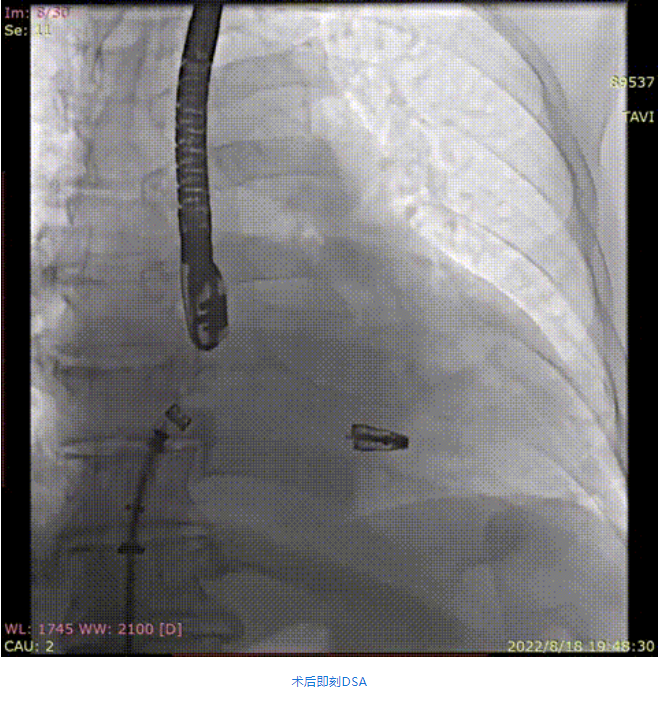

手術(shù)采用全身麻醉插管,經(jīng)股靜脈-房間隔入路,在TEE和DSA引導(dǎo)下完成房間隔穿刺。置入瓣膜夾系統(tǒng)后,在左房調(diào)整瓣膜夾的位置和軸向,后進(jìn)入左室,在TEE引導(dǎo)下捕捉二尖瓣前后瓣葉,并關(guān)閉瓣膜夾。經(jīng)TEE反復(fù)確認(rèn)手術(shù)效果后最終鎖定并釋放瓣膜夾。術(shù)后即刻超聲顯示瓣膜夾位置穩(wěn)定,功能良好,肺靜脈逆流和左房壓都明顯好轉(zhuǎn)。